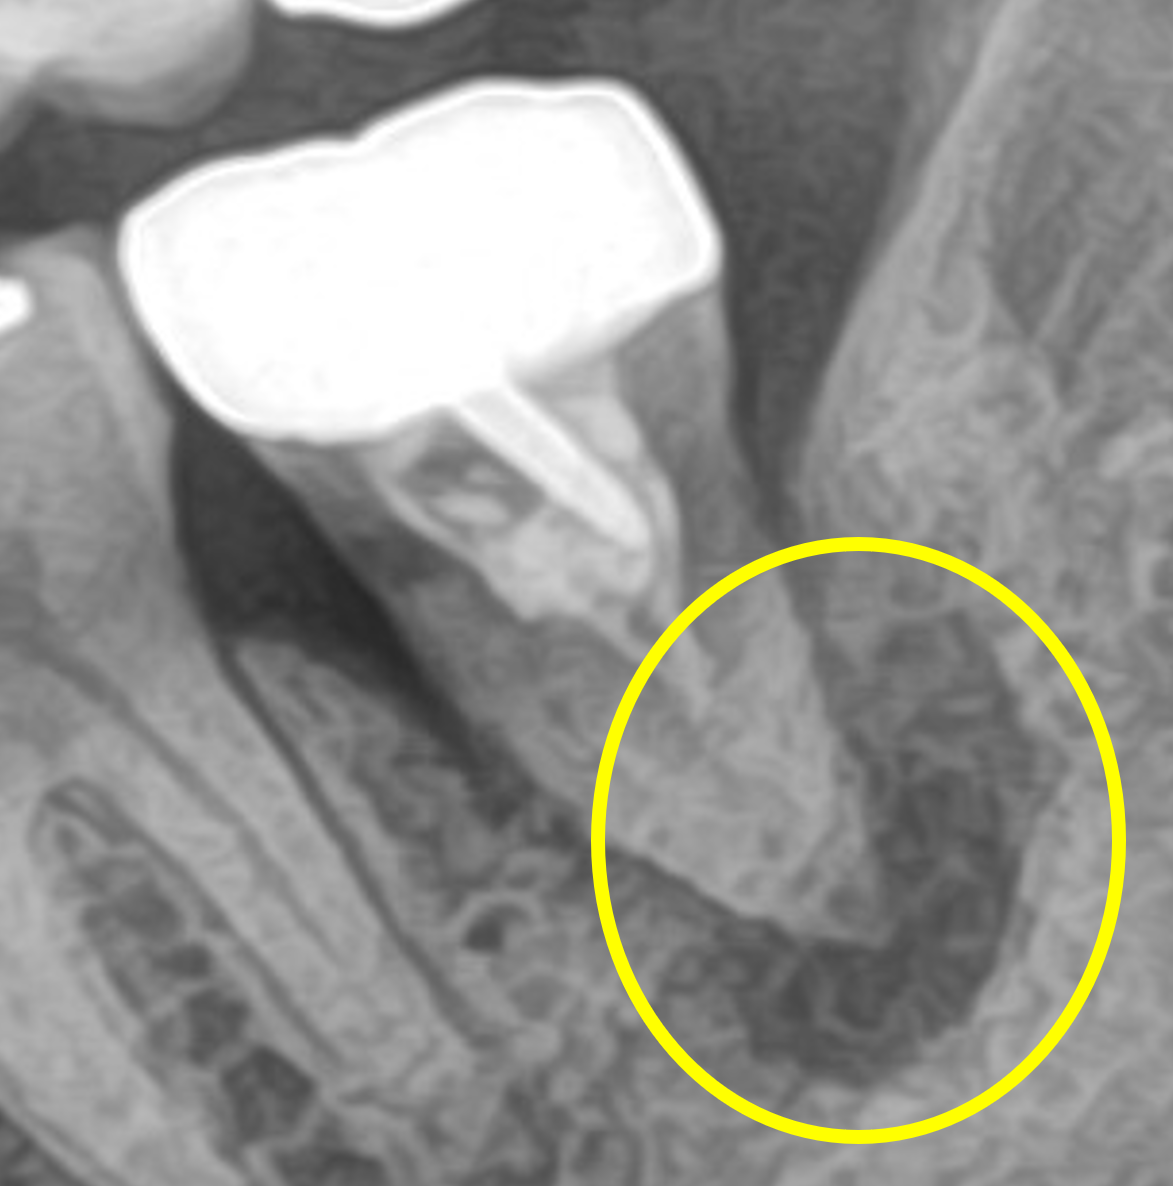

まず、レントゲンを見て予想できることは、以前の治療では顕微鏡(マイクロスコープ)や高倍率ルーペを使わずに肉眼もしくはそれに近い状態で治療したということです。

神経が上の方しか取られておらず、大半が取り残されています。この歯は奥歯の中でも一番奥の歯になります。肉眼ではほとんど見えません。手探りでなんとなくの治療になってしまいます。わからないところは触らずに治療を終わらせるしかないのです。取り残された神経は腐って死んでしまうので、そこから細菌が繁殖し、大きな根の病気を作ります。